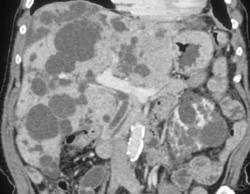

Renal Cancer Simulated An Abscess